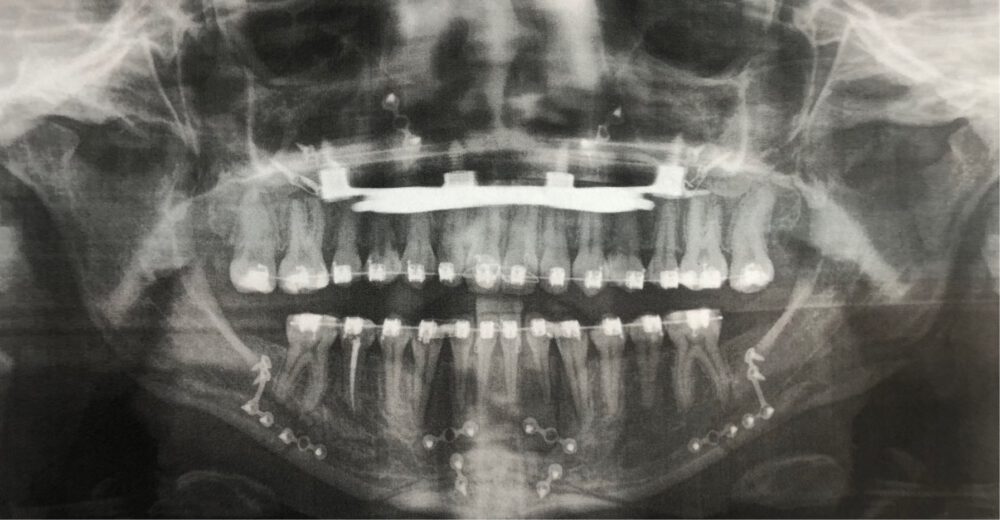

Therapie:

Surgery First: Bignathe Umstellungsosteotomie (Minimalinvasive Le Fort I Osteotomie mit Vorverlagerung und simultaner Oberkieferdistraktion, gesonderte Spina Nasalis Osteotomie zur besseren Kontrolle von Oberlippenposition und -volumen, Anhebung der Nasenspitze, Unterkiefersegmentosteotomie 32-42 zur Vergrößerung der sagittalen Stufe (Dekompensation),

Kinnosteotomie, Side Wing Osteotomie mit Beckenkamminterponat)